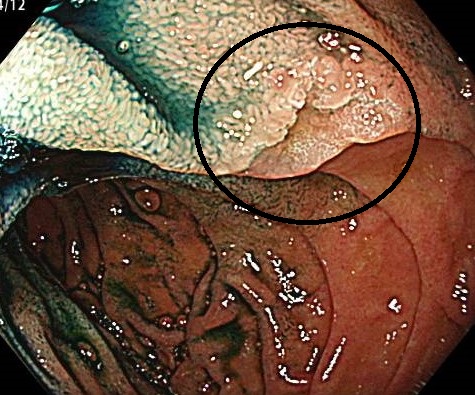

- 早期胃がん(ピロリ除菌後)

除菌後も“0リスク”にはなりません。定期的な内視鏡により早期の段階で病変を捕捉し内視鏡治療で完治。